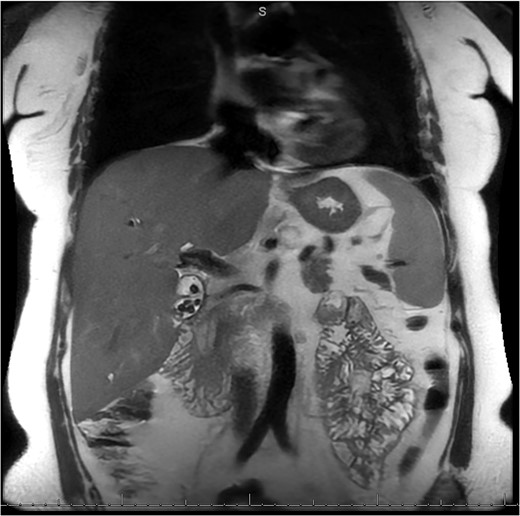

A 49-year-old female with a history of ADPKD and multiple liver cysts, 13-months status post subtotal cholecystectomy, endoscopic retrograde cholangiopancreatography with biliary sphincterotomy and balloon stone extraction, presented to the emergency department with fever and a 4-day history of discomfort in the right upper quadrant. At the time of the initial cholecystectomy, total cholecystectomy could not be performed due to extensive adhesions, and subtotal cholecystectomy with complete evacuation of the stones was done instead. Magnetic resonance cholangiopancreatography (MRCP) done at that time showed a dilated common bile duct (CBD) to 1.5 cm, intra and extrahepatic biliary dilatation, multiple liver cysts measuring up to 2 cm, and multiple stones in the CBD, including at the level of the ampulla (Fig. 1). Computerized tomography scan at the time of the second admission showed acute cholecystitis and she had mildly elevated transaminases, but there was no evidence of cholestasis or pancreatitis. MRCP showed minor proximal intrahepatic biliary dilation and cholelithiasis but no duct calculi (Figs 2–4). A laparoscopic cholecystectomy was attempted with extensive adhesiolysis between the gallbladder and surrounding omentum and mesocolon, but the cystic duct could not be isolated, and ultimately the cased was converted to open. While removing the gallbladder in a top-down fashion, a small bile leak was identified right at the closed end of the gallbladder remnant, where the bile duct was adhered to the gallbladder wall. Intraoperative cholangiogram was obtained through a small perforation in a right posterior bile duct at the site of attachment, which showed right posterior, right anterior and left hepatic ducts of equal size converged at a trifurcation (Fig. 5). The duct was repaired over a T-tube and observed throughout the rest of the case and no bile leak was identified. The gallbladder was opened along its lateral edge, revealing a hugely dilated cystic duct with ~10 to 12 marble-sized stones packed within the gallbladder remnant and cystic duct down to the juncture with the common bile duct. All the stones were removed and the safe portion of the gallbladder remnant was resected leaving the side attached to the bile duct in situ due to the Mirizzi anatomical variant. The cystic duct was oversewn along with the remnant of the gallbladder wall. Pathology showed acute-on-chronic cholecystitis with cholelithiasis. Repeat MRCP showed no retained stones in the biliary tree. The recovery course was unremarkable.

MRCP from initial hospitalization, including cysts in the area of the gallbladder fossa, cholelithiasis, choledocholithiasis and CBD dilation, measured to be 1.5 cm (measurement not included in image).